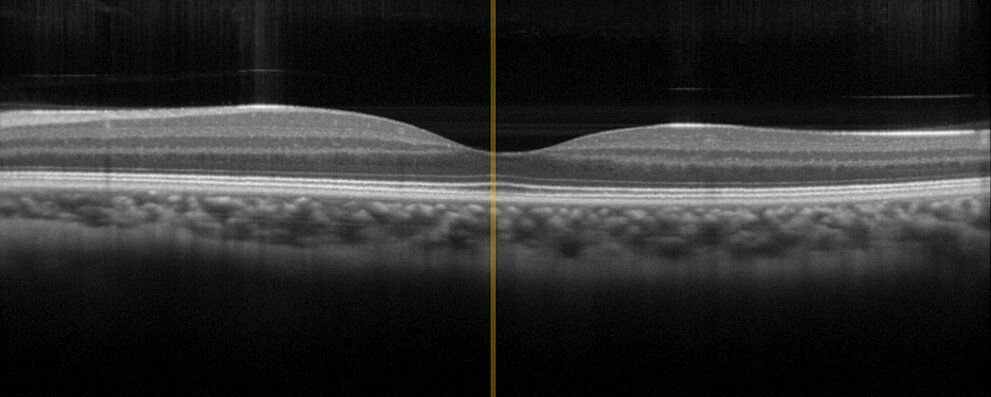

Optical Coherence Tomography (OCT)

Physik Instrumente OCT Test Image

Optical coherence tomography (OCT) makes it possible to examine layers under the skin's surface noninvasively and to create three-dimensional images of the skin structure. This requires precise adjustment of the optics.